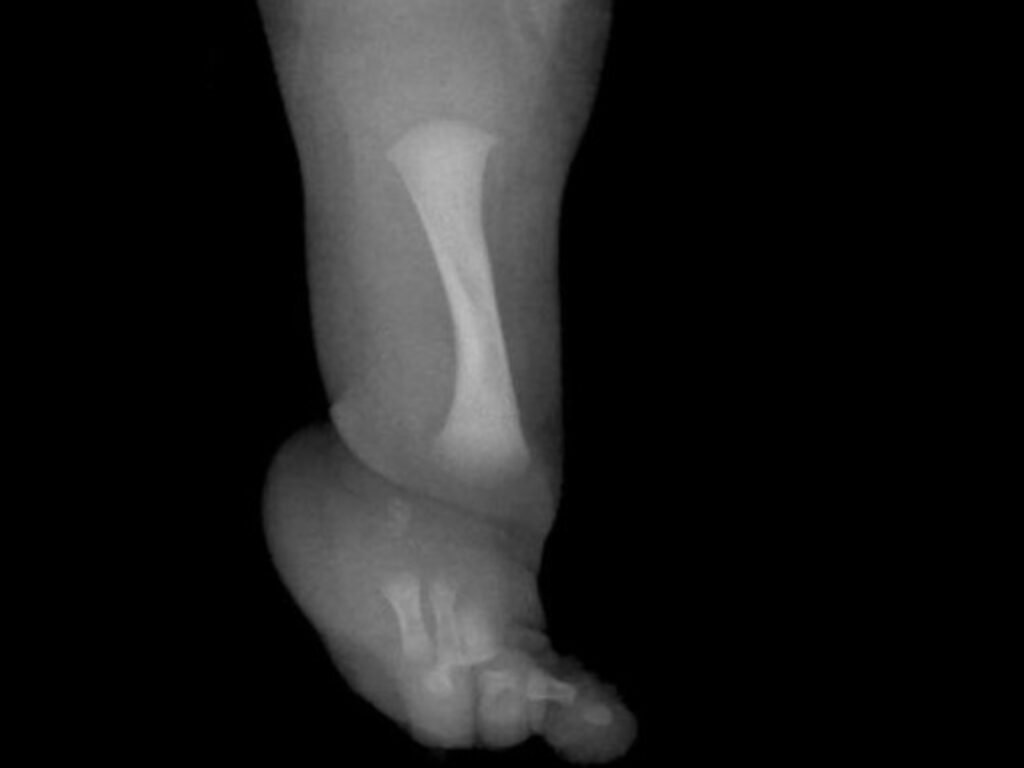

Uncategorized Un nene con una rara enfermedad fue operado para desarrollar un hueso fundamental hace 2 mesesMenos de 1 min22,0 Vistas Un niño de nueve años se ha sometido en el Reino Unido a una cirugía pionera. Es para menores que tengan hemimelia fibular. Acciones: TE RECOMENDAMOS Uncategorized En qué países se descansa más: cuántos días de vacaciones tiene cada uno hace 1 mes Uncategorized ¿A qué hora juega Puerto Rico vs Colombia por el Clásico Mundial de Béisbol 2026? Horarios por país este 6 de marzo y cómo ver EN VIVO el partido por el WBC hace 1 mes Uncategorized Clima hoy en Los Reyunos, Mendoza: el pronóstico del tiempo para este martes 13 enero de 2026 hace 3 meses Uncategorized Bad Bunny Performs First Asia Concert at Star-Studded Spotify’s Billions Club in Tokyo hace 1 mes Uncategorized Quiniela de la Provincia: resultado del sorteo de la Nocturna de hoy, viernes 19 de diciembre hace 4 meses